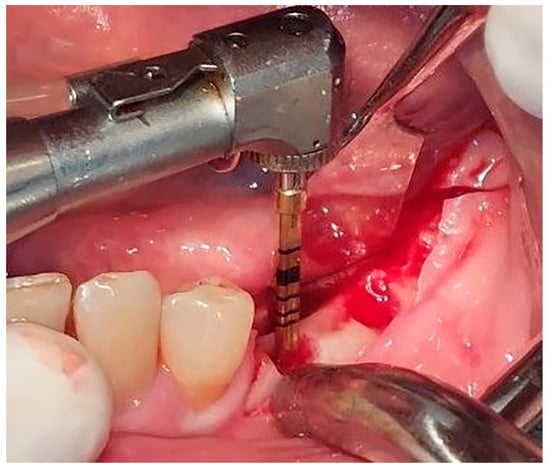

Local anesthesia using 4% articaine with adrenaline 1:100,000 (Septanest®, Septodont, Saint-Maur-des-Fossés, France) was administered. After the midcrestal longitudinal incision, a full thickness mucoperiosteal flap without a vertical releasing incision was elevated and the top of the alveolar ridge was flattened to the width of 4 mm (Figure 3). Preparation of the implant bed was performed with only one twist drill from the set (Esset kit®, Osstem, Seoul, Republic of Korea) which corresponded to the implant length (Figure 4). Following the preparation of the implant bed with the twist drill, a midcrestal longitudinal osteotomy was performed with a special saw with the speed of 1200 rpm (Figure 5). A specially designed set of expanders (Esset kit®, Osstem, Seoul, Republic of Korea) was used gradually in order to separate the buccal plate from the lingual cortical plate, according to their elasticity (Figure 6A–C).

Figure 3. Flattening of the top of the alveolar crest to the level of 4 mm.

Figure 4. Preparation of the implant bed.